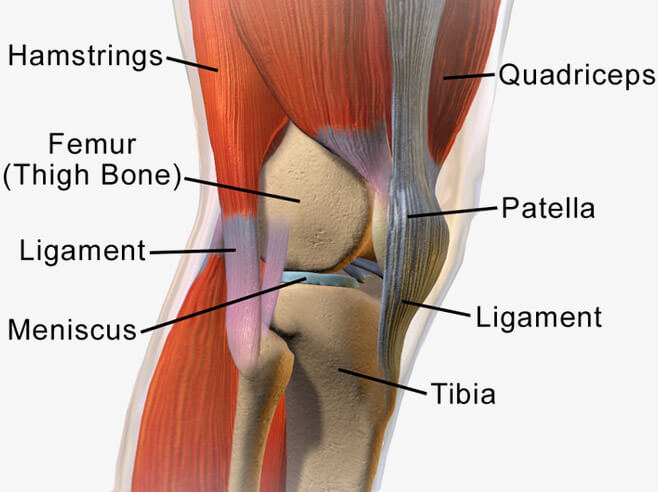

The knee is one of the strongest joints in the human body. The knee joint is also known as the tibiofemoral joint and is composed of three bones: the femur (thigh bone), the patella (knee cap), and the tibia (shin bone). Together, these bones come together to form a synovial hinge joint that allows flexion and extension of the leg.